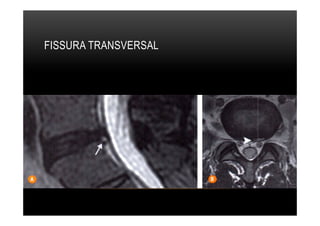

FISSURA TRANSVERSAL

•  Transversal, também conhecidas como periféricas, são as rupturas horizontais das

fibras de Sharpey, próximo à inserçào apofisária do anel fibroso.